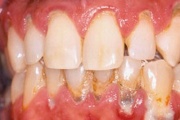

Krooniline parodontiit

Krooniline parodontiit on mikroobide poolt põhjustatud hammaste tugikudede põletik, mille tulemusena tekib progresseeruv alveolaarluu (nähtav röntgenograamil) ja periodontaalligamendi destruktsioon, igemetaskute moodustumine, igeme retsessioon või mõlemad kahjustused kombineeritult. Loe edasi »

- puudulik suuhügieen (5)

- igemepealne hambakivi (5)

- igemealune hambakivi (4)

- halb hingeõhk / suu haiseb (12)

- halb maitse suus (12)